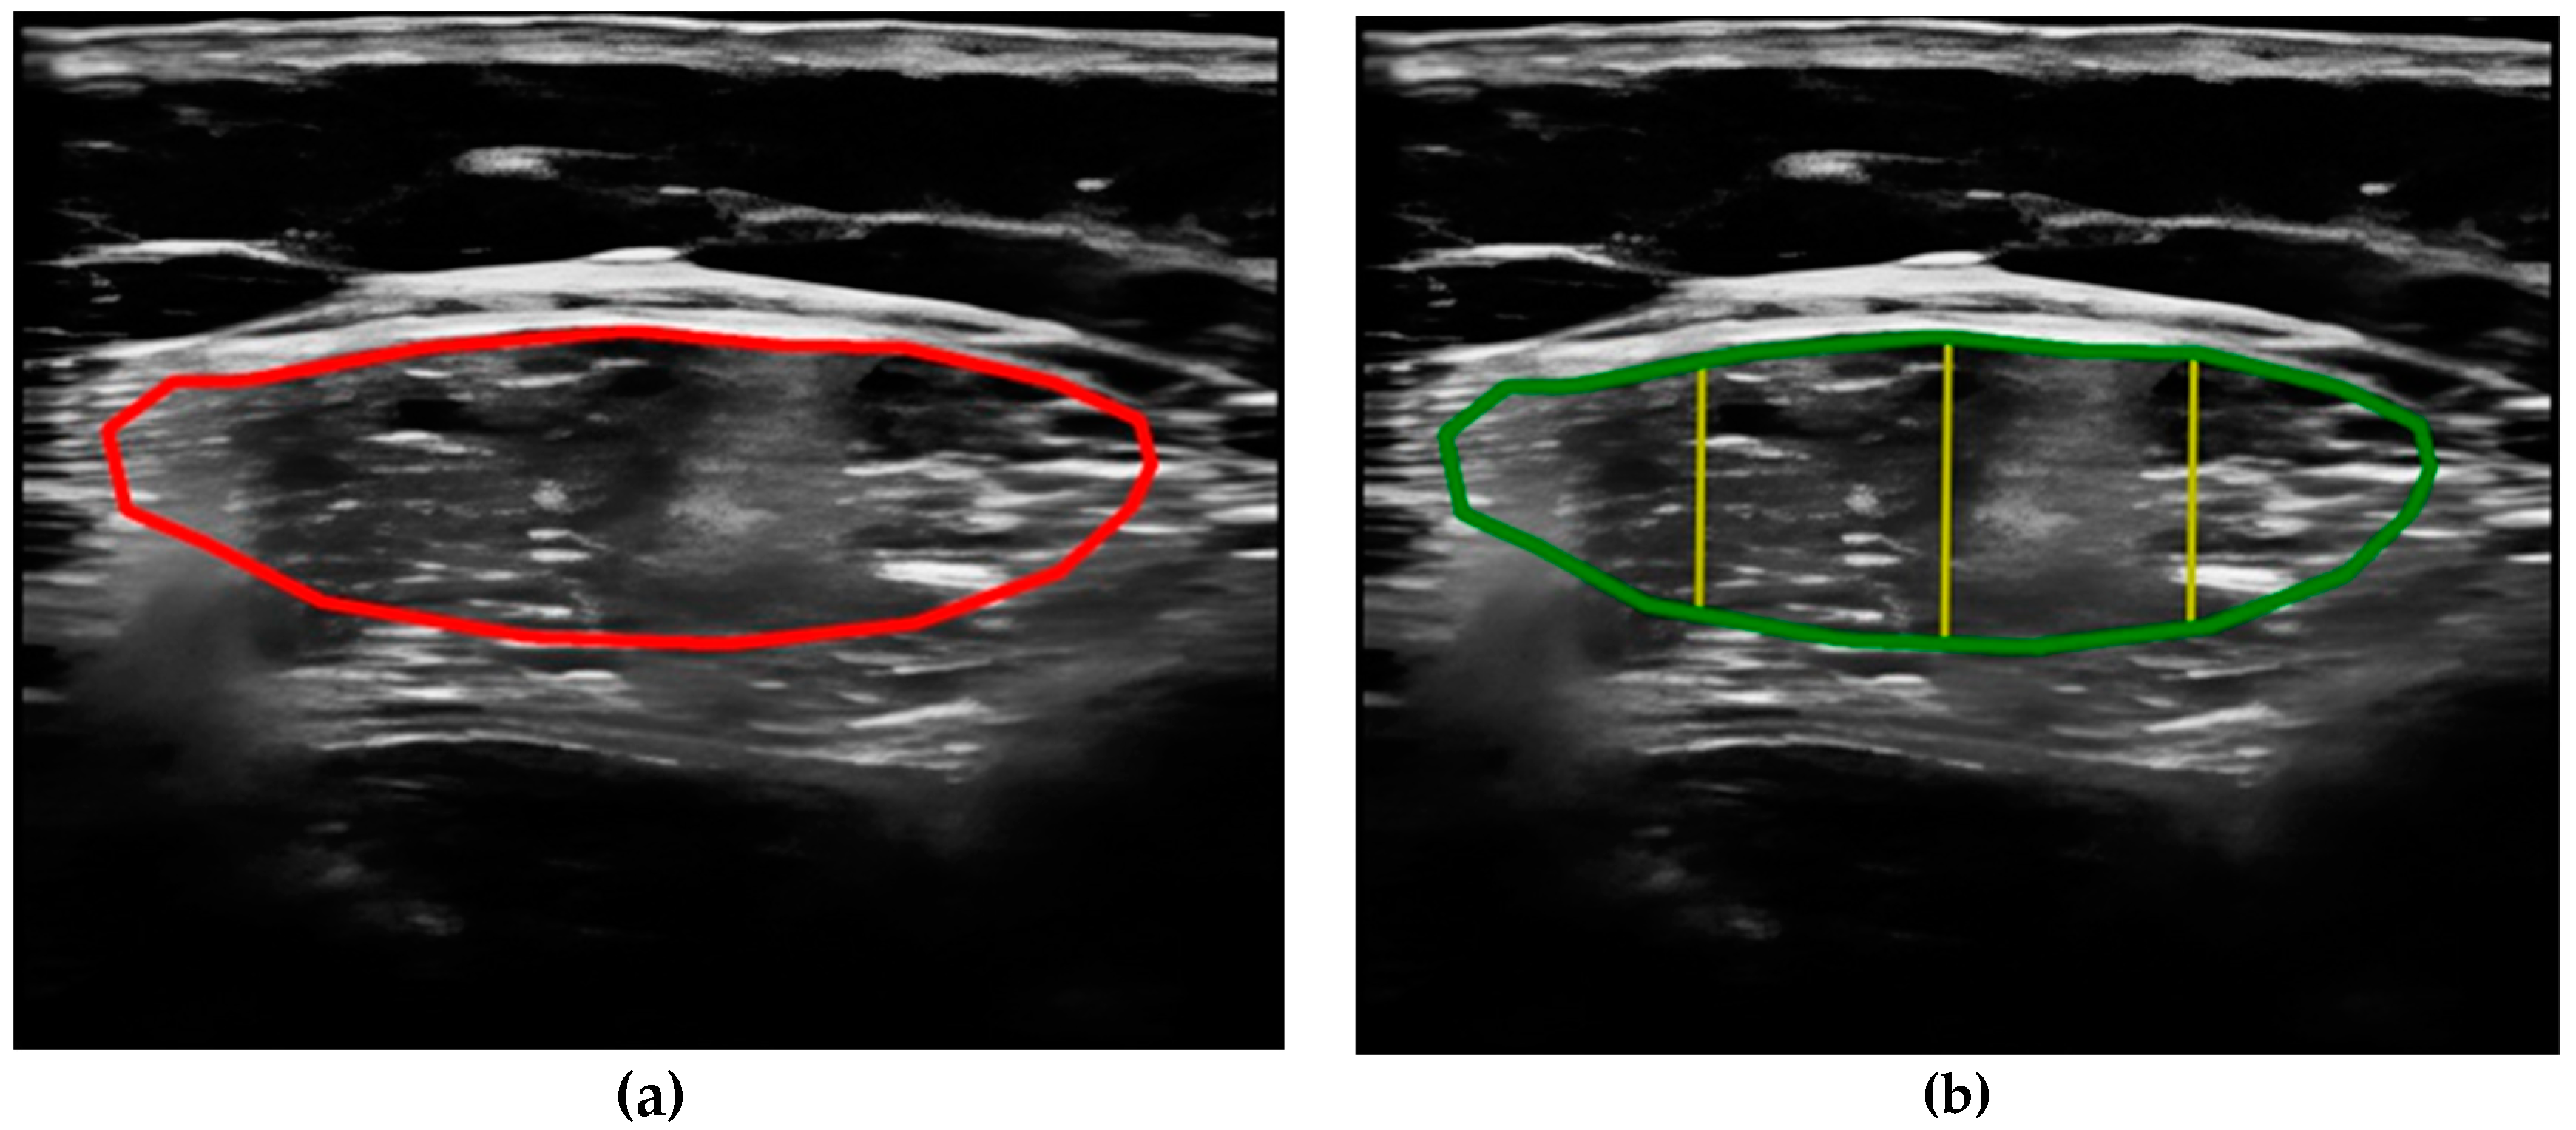

- Compare the measurements of the unilateral (right) RF of the patients performed by the expert evaluator (rater 1) using the standard tools included in the ultrasound image device (i.e., method A), see Figure 2, with those obtained by applying the PIIXMEDTM Ultrasound Imaging System (Dawako Medtech S.L., Valencia, Spain) (rater 2) (i.e., method B) [15,16,17,18,19] on the same acquired raw images, see Figure 3 and Figure 4.

Figure 3. (a) Acquired raw ultrasound image of the unilateral (right) quadriceps rectus femoris muscle in the transverse plane obtained by rater 1, scaled and automatically segmented (red color line) by PIIXMEDTM (rater 2—method B); (b) PIIXMEDTM processing (i.e., rater 2—method B) of the segmented transverse ultrasound image to obtain the results of CSA (green color), and MT (three yellow lines and their mean value) parameters.